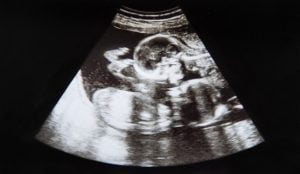

اختفى جنين طفلة في رحم أمها، لكنها تركت لشقيقها التوأم، علامة تشبه صورتها الخاصة على جسمه.

ولدى بايلون غيفنز علامة مميزة على ركبته على شكل حبة “الكاجو”، على غرار شكل شقيقته التوأم، عندما تم فحصهما في الرحم في الأسبوع العاشر من الحمل.

وأضافت: “لم يكن الأمر غريبا بالنسبة لي، لقد كان شعورا رائعا .. إن العلامة تشبه فحص أخته خلال 10 أسابيع من الحمل، سيكون ذلك تذكيرا لبايلون بتوأمه التي لم تنمُ”.